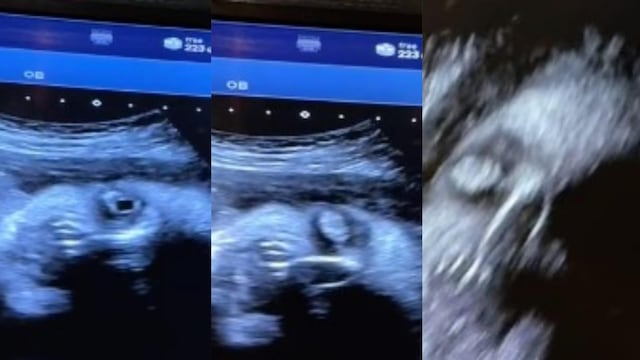

En TikTok se han viralizado varios videos que dan bastante miedo, pero ahora un usuario ha revelado cómo en un ultrasonido de un bebé se muestra una cara demoníaca.

En un video de un ultrasonido ha aterrorizado a TikTok, pues claramente se puede ver cómo el bebé toma la forma de un demonio en la pantalla.

Si bien en ocasiones no siempre se les encuentra una forma concreta a un ultrasonido de un bebé, en este claramente se le ve una cara demoníaca.

Luego de que se hiciera viral el video del ultrasonido de un bebé en donde aparece una cara demoníaca durante su semana 32, los usuarios han reaccionado a él.

Pues claramente en el ultrasonido puede apreciarse como una cara de bebé se va transformando en una más diabólica.